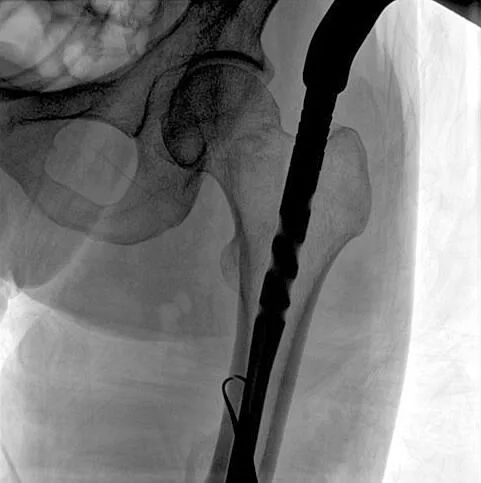

C形臂輔助手術過程

術中使用普愛醫療大平板一體式C形臂進行透視,判斷骨折情況及克氏針、髓內釘等金屬植入物的位置,進行調整。C形臂準確的術中定位,大大縮短了手術的時間,減輕了患者的痛苦,輔助手術順利完成。

術中定位準確、出血量少,術后影像顯示股骨移位糾正,恢復良好力線,手術效果良好。